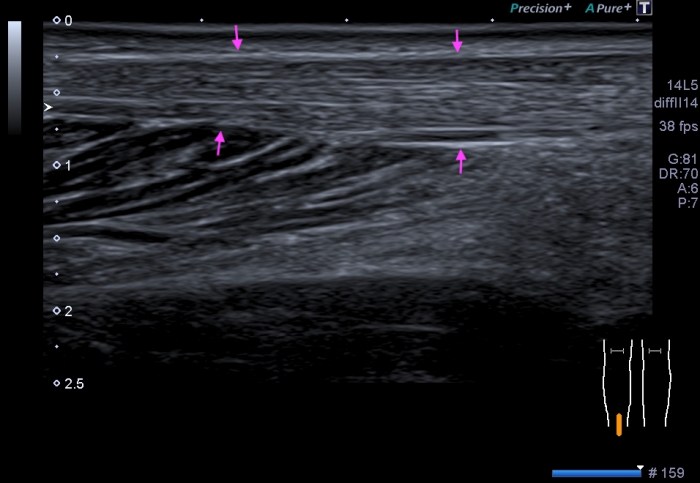

La imagen que debes de conseguir en una imagen normal del hígado es el en lóbulo hepático derecho y sería esta:

La imagen típica de hepatopatía crónica sería esta:

Puedes observar la superficie hepática en forma de olas y la heteroecogenicidad del hígado..

Compara la dos imágenes y percibe los cambios, así podrás reconocer siempre estos cambios.